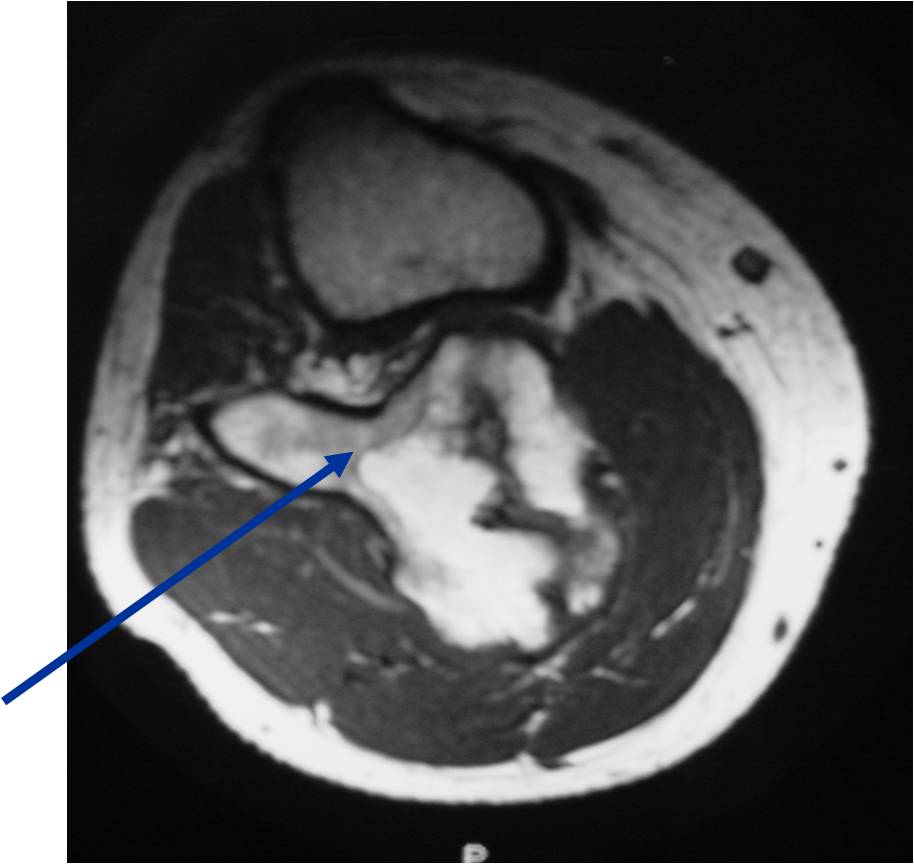

- Best test for evaluating thickness of cap and surrounding bursa

- Intermediate T1W Images

- High Intensity T2W Images because of fluid content

MRI: Secondary Chondrosarcoma of Proximal Femur: Thick Cartilage Cap (>2cm)